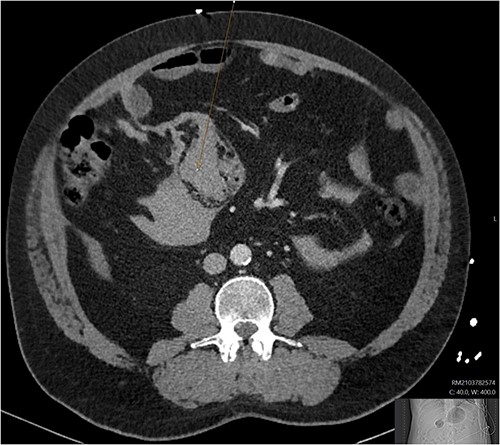

During admission the patient’s abdominal pain gradually improved, his Hb increased and he had no further coughing episodes. The patient was therefore stepped down to oral antibiotics and considered safe for discharge. A CT-AP four weeks post-discharge demonstrated a persisting 60 x 40 mm liquefying haematoma in the small bowel (Fig. 4), resolution of the peri-hepatic haematoma (Fig. 5) and interval reduction of the peri-splenic and pelvic haematomas. Given these improvements and the patient’s lack of significant symptoms, a plan to actively survey his progress was made.

Follow up CT angiogram showing improvement in mesenteric haematoma. Figure 4 is an axial section from the patient’s CT scan performed 4 weeks following discharge. The arrow highlights the patient’s liquefying mesenteric haematoma, which decreased from 104 x 62 mm to 60 x 40 mm. Combined with the improvement in the other areas of intra-abdominal bleeding and the patient’s overall clinical state, this image represents a significant improvement.

Follow up CT angiogram showing improvement in perihepatic haematoma. Figure 5 is another axial section from the patient’s CT angiogram performed 4 weeks following discharge and shows resolution of the perihepatic haematoma seen previously. Together with the other sections of the CT angiogram and the patient’s overall clinical state, the image represents a significant improvement in the patient’s intra-abdominal bleeding.